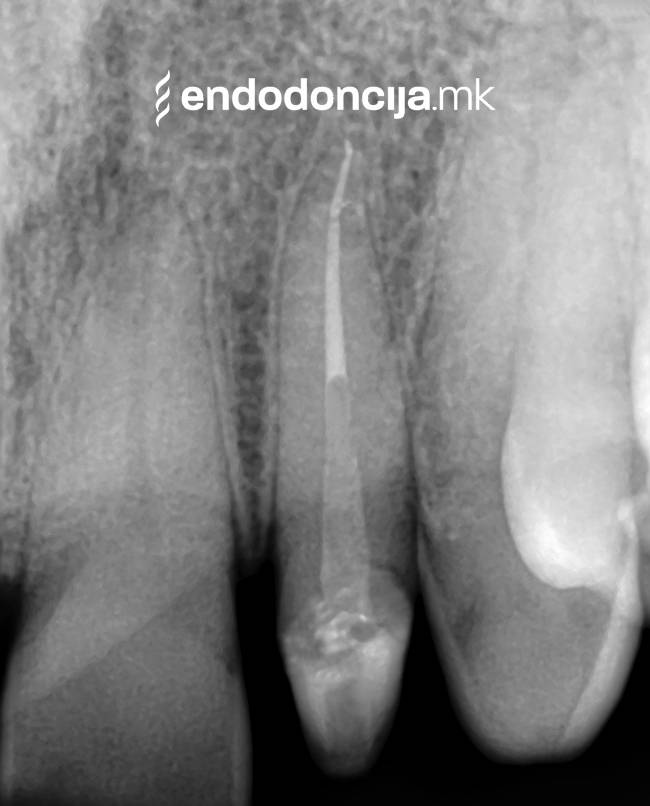

Εκτός από την ανίχνευση των ριζικών καναλιών, η ενδελεχής προετοιμασία και η απολύμανση του ριζικού σωλήνα είναι η προϋπόθεση για μια επιτυχημένη συνολική θεραπεία. Μέσω της χρήσης των νεότερων οργάνων και αντιβακτηριακών διαλυμάτων, όλα τα υπολείμματα ιστών και τα βακτήρια που υπάρχουν μπορούν να εξαλειφθούν.

Κατά τη διάρκεια της επεξεργασίας του ριζικού σωλήνα, τα λεπτά όργανα ενδέχεται να σπάσουν. Αυτό μπορεί να αποτελέσει εμπόδιο για την πλήρη προετοιμασία και τον καθαρισμό του ριζικού σωλήνα. Με μια μικροσκοπική επεξεργασία του ριζικού σωλήνα μπορεί να είναι δυνατή η απομάκρυνσή τους υπό ορισμένες συνθήκες, χωρίς να καταστρέφεται η ουσία των δοντιών.